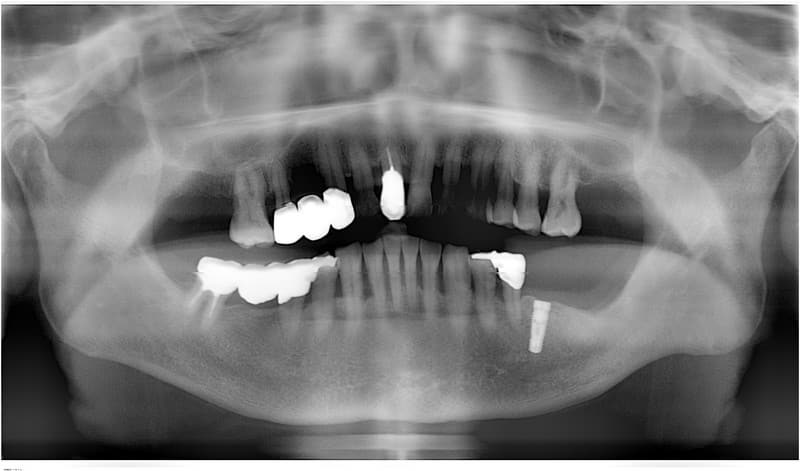

臼歯部から歯が欠損している場合(遊離端)

従来の治療

部分入れ歯で治療。

健康な隣の歯に維持のための鉤をかけるため、歯に負担がかかります。

インプラント治療

必要な本数のインプラントを埋入し、それぞれ単独で治療するか、インプラント同士を連結したブリッジとする。